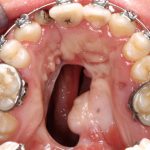

این کار بر روی یک نوجوان ۱۶ ساله انجام گرفت که به دفعات و روشهای متعدد در مراکز دیگر تحت درمان جراحی شکاف کام قرار گرفته بود، لکن به علت گستردگی شکاف درمان ایشان ناموفق بود .به پیشنهاد آقای دکتر احمد بهروزیان عضو هیات علمی بخش ارتدنسی و همکاری آقای دکتر مرتضوی طرح درمان وی ریخته شد. بنا به اظهارات آقای دکتر بهروزیان در قدم اول ، ارتودنسی و آماده سازی به مدت سه سال برای ایشان انجام شد و سپس طراحی قطعه تیتانیومی آغاز گردید. در این روش بعد از اسکن سه بعدی جمجمه بیمار، قطعه در نرم افزار کامپیوتری به صورت مجازی طراحی شد و بعد از بررسی ها و اندازه گیری های لازم به صورت تراش سه بعدی از بلوک تیتانیومی در یکی از شرکتهای دانش بنیان داخلی تولید گردید.

جراحی برای جاگذاری اپلاینس توسط آقای دکتر علی مرتضوی عضوهیات علمی بخش جراحی دهان ، فک و صورت دانشکده انجام شد. بنا به اظهارات ایشان ، این روش به صورت ابداعی بوده و بعد از حصول نتایج موفقیت آمیز برای سایر بیماران نیز به مورد اجرا گذاشته خواهد شد.ایشان اظهار داشتندهم اکنون وضع بیمار مطلوب بوده و بیمار بعد از دو روز می تواند به زندگی عادی برگشته و نتیجه نهایی بعد از دو هفته از عمل جراحی مورد انتظار است.